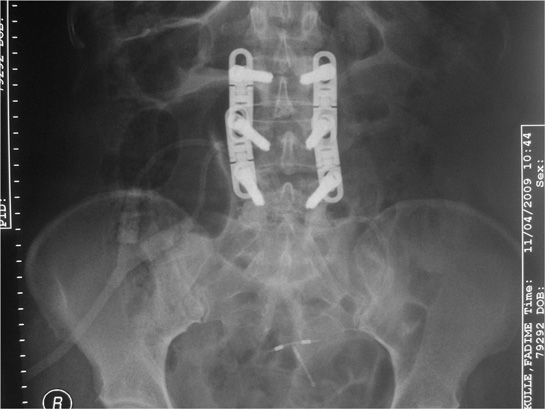

Bele Platin Takılması

Bele Platin Takılması Bele platin takılması, bel bölgesinde meydana gelen yaralanmaların, kırıkların veya dejeneratif hastalıkların tedavisinde kullanılan cerrahi bir yöntemdir. Bu işlem, omurganın stabilitesini artırmak ve ağrıyı azaltmak amacıyla gerçekleştirilir. Bu makalede, bele platin takılmasının nedenleri, prosedürü, iyileşme süreci ve olası komplikasyonları ele alınacaktır. 1. Bele Platin Takılmasının Nedenleri Bele platin takılması, çeşitli tıbbi durumlar nedeniyle gerekli hale gelebilir. Bu nedenler arasında şunlar bulunmaktadır: